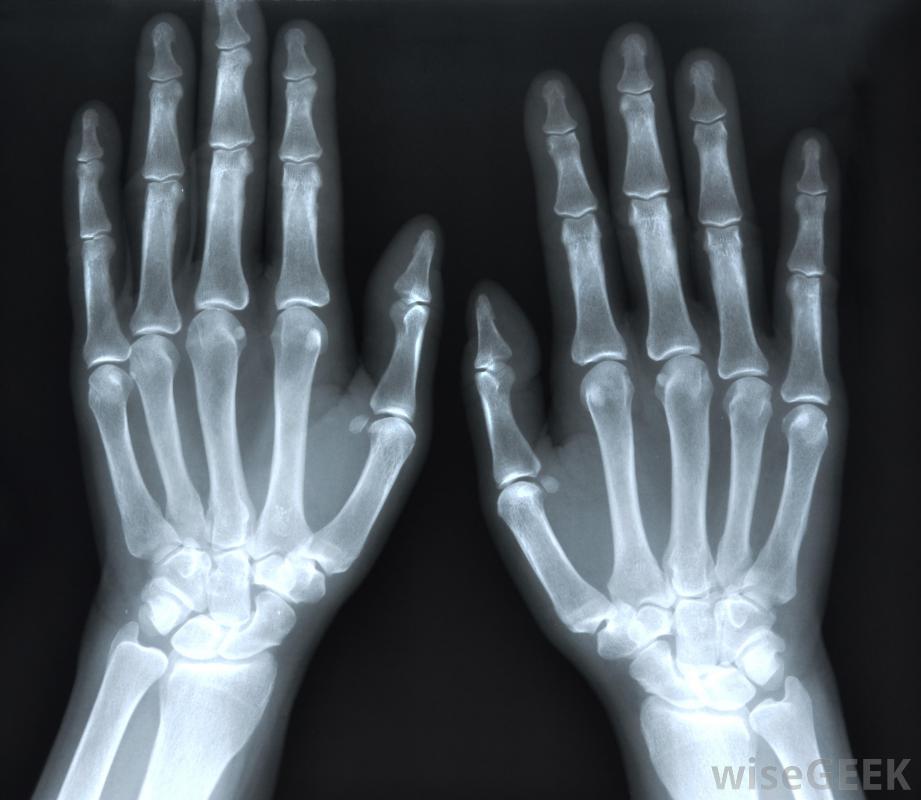

骨刺和关节炎可以通过X光片诊断。